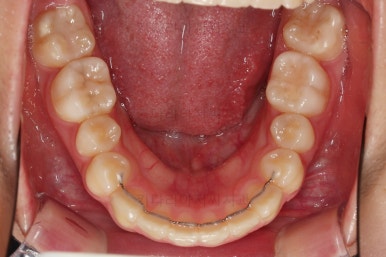

연산동치과 초진 시, 입안의 모습입니다.

보시다시피 앞니쪽이 많이 삐뚤고요. 어금니쪽이 긴밀하지 못한 부정교합이 있네요.